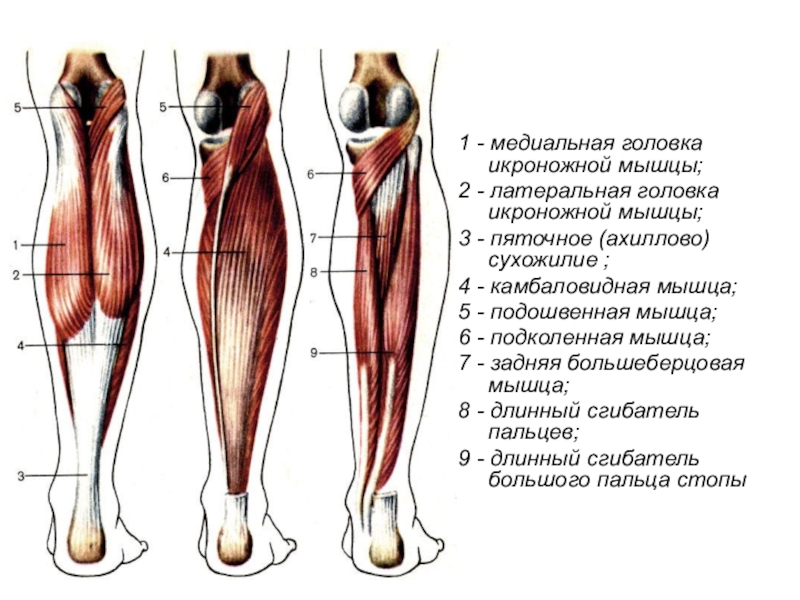

Слайд 631 - медиальная головка икроножной мышцы;

2 - латеральная головка икроножной мышцы;

- пяточное (ахиллово) сухожилие ;

4 - камбаловидная мышца;

5 - подошвенная мышца;

6 - подколенная мышца;

7 - задняя большеберцовая мышца;

8 - длинный сгибатель пальцев;

9 - длинный сгибатель большого пальца стопы